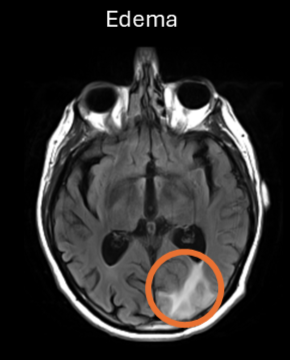

ARIA-E is caused by increased extravasation of protein-rich fluid resulting in vasogenic edema and/or effusion. MRI changes are best detected as bright signal on T2-fluid-attenuated-inversion recovery (T2-FLAIR) sequences.

ARIA-E rating is based on the largest in-plane diameter of the largest T2-FLAIR finding, with cut-offs < 5 cm, 5-10 cm and > 10 cm to define mild, moderate and severe stages. Studies have shown that whether you use the basic 3‑level scale (mild, moderate, severe) or the more detailed 5‑level scale (mild, mild +, moderate, moderate +, severe), the ratings agree closely with those from a fully region‑by‑region scoring system.

| ARIA-E (sulcal or [sub]cortical) | 1 location <5 cm | 5 – 10 cm OR ≥ 1 location | > 10 cm |